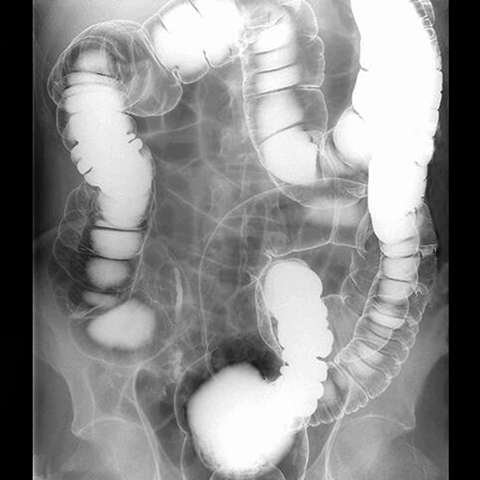

Air constrast barium enema [2 of 2]